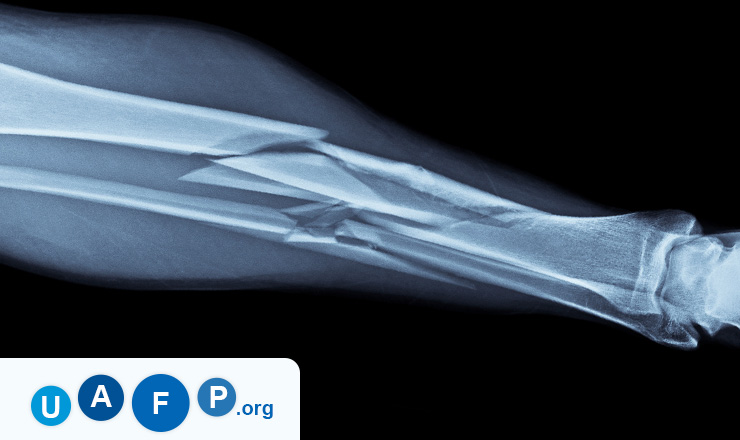

Most people experience a broken bone in their lifespan. We are not aware of how the broken bone heals. Let us look at the healing process of the bone. Our body starts healing the broken bone immediately. The healing process depends on the age and location of the broken bone. The healing process is similar to all the bones. After a bone is broken within the first few hours a blood clot is formed around the broken bone and certain special cells clean the bone fragments. These cells are known as phagocytes and are part of the immune system. These cells capture and destroy the unwanted bacteria and other materials. A soft callus made of collagen is created around the fracture. The minerals are added to the callus to form a hard callus which will help create new bone. The whole process can take anywhere from 6 to 12 weeks. Slowly over the years the bone is remodeled and healed completely. The remodeling is a slow process and can take anywhere between 3 to 9 years to get the bone back in the shape.